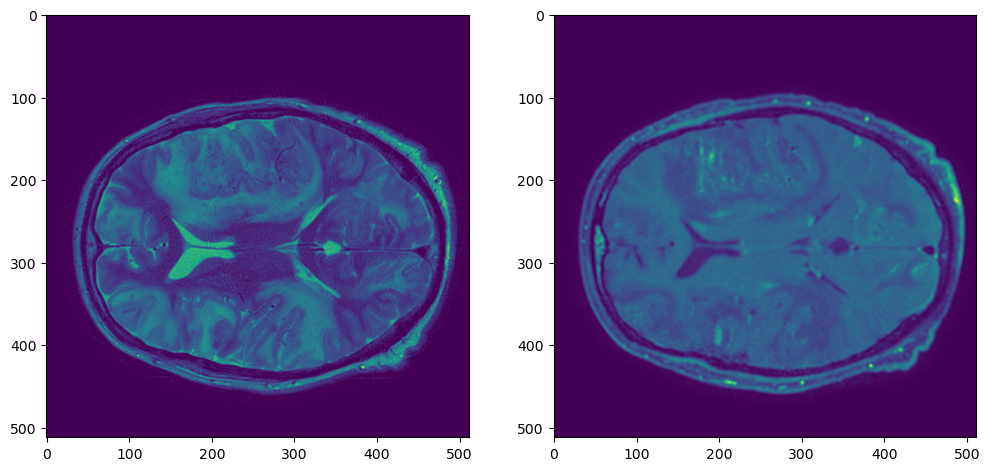

t1t2

Давайте воспользуемся для этого готовой функцией resample_img из библиотеки nilearn.

t1_resampled = resample_img(t1_nib, target_affine=t2_nib.affine, target_shape=t2_nib.shape)

t1t2resampled

Работает довольно медленно, но есть решение быстрее.